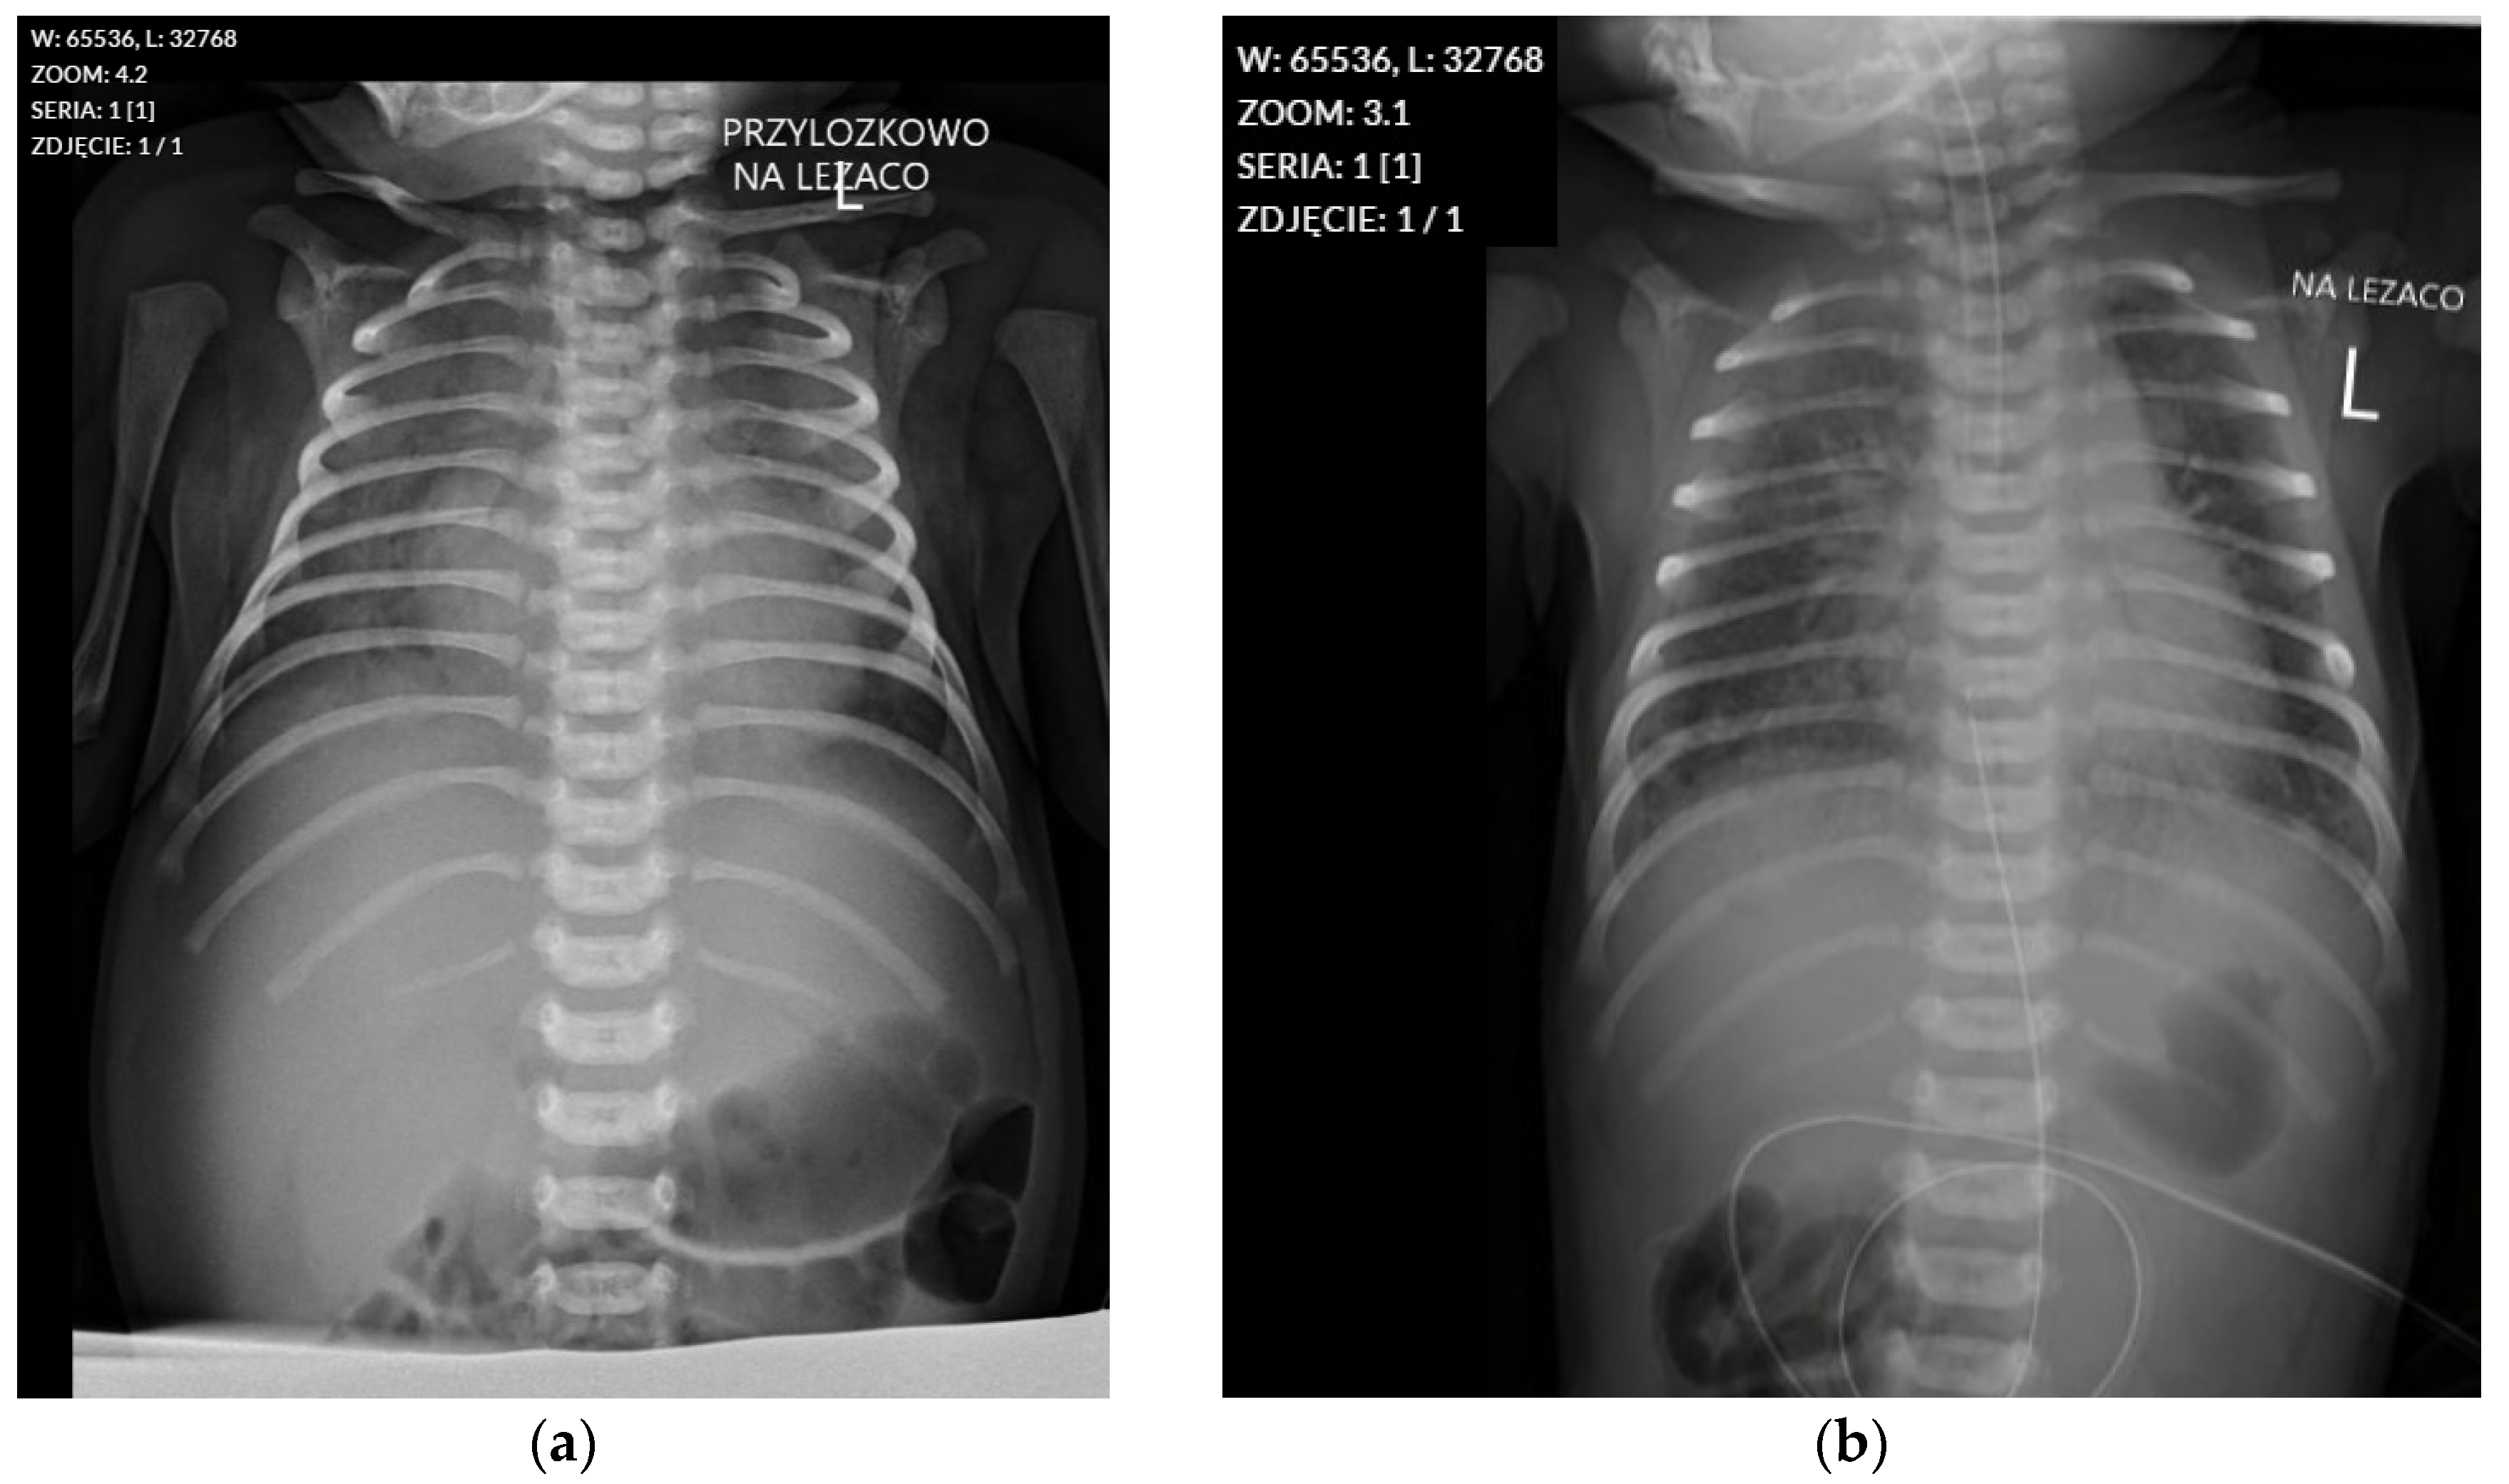

Due to meconium aspiration, MAS (Meconium Aspiration Syndrome) developed, leading to severe pulmonary hypertension, which was treated with nitric oxide (NO) from day 4 to day 9 of life. Chest radiographs performed on days 1 and 4 (Figure A1) of life revealed ground-glass opacities in both lung fields, consistent with severe Respiratory Distress Syndrome (RDS), with a noticeable progression of changes on the follow-up examination (Table A3). From admission, mechanical ventilation requiring high pressures (PEEP 8 cm H2O, PS 18 cm H2O) and 100% oxygen was used. After stabilisation of circulatory and respiratory conditions and a reduction in pulmonary hypertension symptoms, the patient was extubated on day 12 of hospitalisation. Due to the patient’s ongoing respiratory distress, non-invasive ventilation was continued until day 20 of life.

The following figure and table present the results of serial chest X-ray examinations performed on the patient, documenting the progression of changes in the lungs over the first days of life. These data are provided as appendixto the main text.

Figure A1.

Chest radiographs from 26 August and 29 August 2022. (a) Chest radiograph from 26 August 2022, showing ground-glass opacities in both lung fields, consistent with Respiratory Distress Syndrome. (b) Follow-up chest radiograph from 29 August 2022, demonstrating progression of the ground-glass opacities and mild cardiomegaly.

Results of serial chest X-ray examinations.

| Date of Examination | Results of Chest X-Ray Examination |

|---|---|

| Day 1 of life | Lungs: Increased interstitial pattern described as a “ground-glass opacity” (features of RDS) in both lung fields, perihilar. No other focal changes in the lung fields. Heart: Cardiac and major vessel shadows within normal limits. Other: The tip of the endotracheal tube is in a low position (approx. 4 mm above the tracheal bifurcation). |

| Day 3 of life | Lungs: Ground-glass opacification of both lung fields, with an increased interstitial pattern resembling “ground glass”. No focal changes in the lungs. Progression of changes noted compared to the examination on 26.08.2022. Heart: Cardiac shadow is slightly enlarged. Other: The tip of the endotracheal tube is in a correct position. The nasogastric tube tip is located high at the level of the cardia. The tip of the catheter inserted through the umbilical vein is in a high position, at the level of ThVII/ThVIII. |